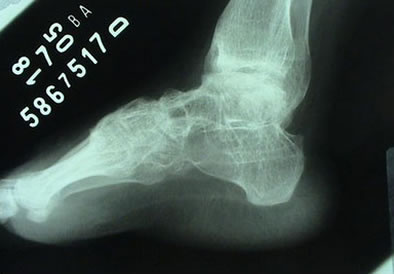

Artroscopia para Artrose do Tornozelo

Durante a artroscopia para artrose, verificamos e tratamos várias lesões. Realizamos sinovectomia, desbridamento e retirada de corpos livres, conforme citado anteriormente. A abrasão do osso subcondral exposto e o restabelecimento dos canais de vascularização e formação de fibrocartilagem podem trazer benefícios. O desbridamento artroscópico na artrose de tornozelo é um procedimento paliativo, que visa alívio temporário da dor em pacientes que ainda apresentam alguma amplitude de movimento. Sendo assim, se houver indicação para artrodese via artroscópica, removemos toda a superfície articular do pilão tibial, domo talar e superfícies talomaleolares medial e lateral (cruentizadas) com shaver e curetas até a exposição de osso esponjoso viável. Tomamos os devidos cuidados para evitar retirada excessiva de cartilagem e osso subcondral, que podem criar deformidades em varo ou valgo. Deformidades angulares prévias podem ser corrigidas artroscopicamente ou via aberta.

Ressecamos o osteófito anterior para possibilitar a redução do domo talar na articulação do tornozelo. Após preparar a área a ser artrodesada, inserimos dois guias canulados para o drill, um lateralmente através do maléolo lateral e um medialmente, através do maléolo medial. Porém, a angulação dos guias canulados será de 30° inferior e 30° anterior, partindo dos maléolos. Utilizamos fluoroscopia para verificar a posição correta da artrodese. No plano sagital, desejamos a posição neutra de dorsiflexão e flexão plantar do tornozelo e no plano coronal o calcâneo deve estar em 5° de valgo. Finalmente, utilizando parafusos canulados de 6,5mm através do guia, concluímos a artrodese.